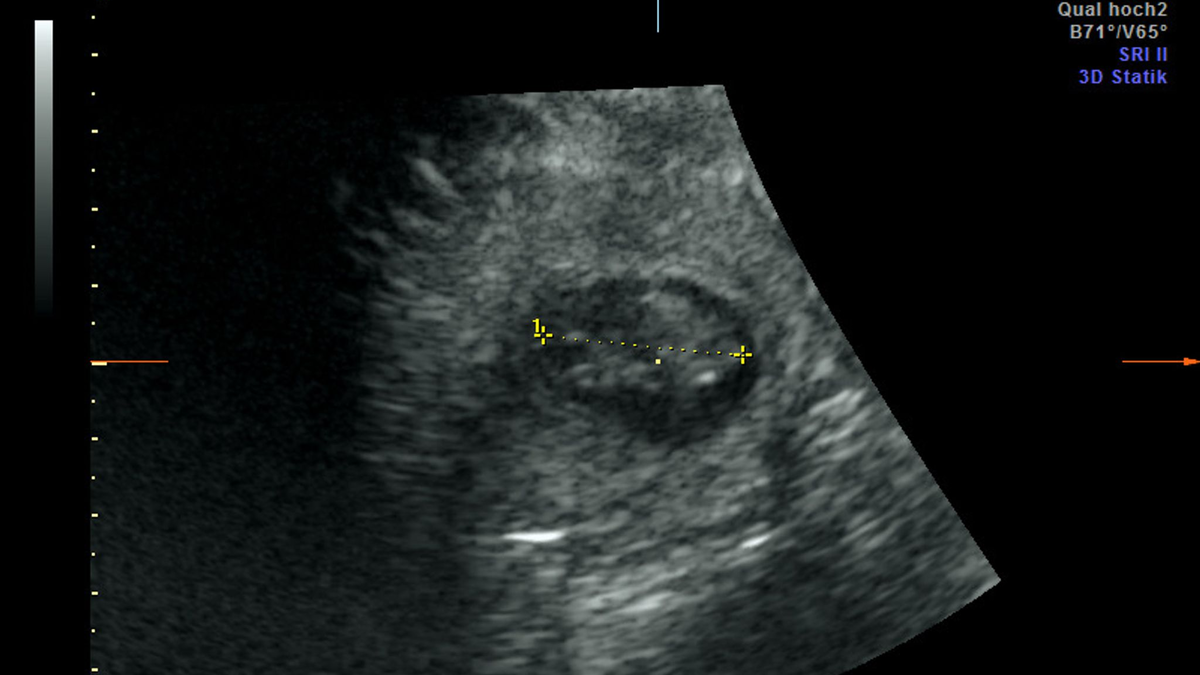

13.08.2024 - 08:49:13Nach fünf Jahren wird im Berliner Zoo wieder Panda-Nachwuchs erwartet. Das Pandaweibchen Meng Meng ist mit zwei Jungtieren trächtig, wie der Zoo am Dienstag mitteilte. «Nach Wochen gespannten Hoffens brach am Sonntagmorgen im Panda Garden des Zoo Berlin ein kleiner Jubel aus. Erst war ein Herzschlag, kurz darauf sogar ein zweiter auf dem Ultraschallgerät zu erkennen.» Die Pandababys seien etwa 2,5 Zentimeter groß und müssten bis zur Geburt jetzt noch ordentlich wachsen.

Kühles Ultraschall-Gel auf Panda-Bauch

Bei Ultraschall-Untersuchungen auf eine mögliche Schwangerschaft habe sich das Pandaweibchen zuletzt nicht besonders kooperativ gezeigt. Am Sonntag sei es aber gut gelaufen. «Trotz sichtlichen Bauchkneifens ließ sich Meng Meng überzeugen, in den aufrechten Stand zu kommen und das kühle Ultraschall-Gel sowie die Untersuchung mit der Ultraschall-Sonde zu akzeptieren», teilte Thomas Hildebrandt, Leiter der Abteilung für Reproduktionsmanagement am Leibniz-Institut für Zoo- und Wildtierforschung, mit. Die Untersuchung im Stehen habe schließlich die freudige Nachricht gebracht, dass Meng Meng trächtig sei.

Die Freude im Team sei riesig gewesen, weil es schon einige erfolglose Ultraschallversuche gegeben habe, sagte die Zootierärztin Franziska Sutter, die ebenfalls an der Untersuchung beteiligt war. «Bei aller Begeisterung müssen wir uns darüber im Klaren sein, dass das ein sehr frühes Stadium der Trächtigkeit ist und eine sogenannte Resorption – also ein Absterben - des Embryos zu diesem Zeitpunkt noch möglich ist.»